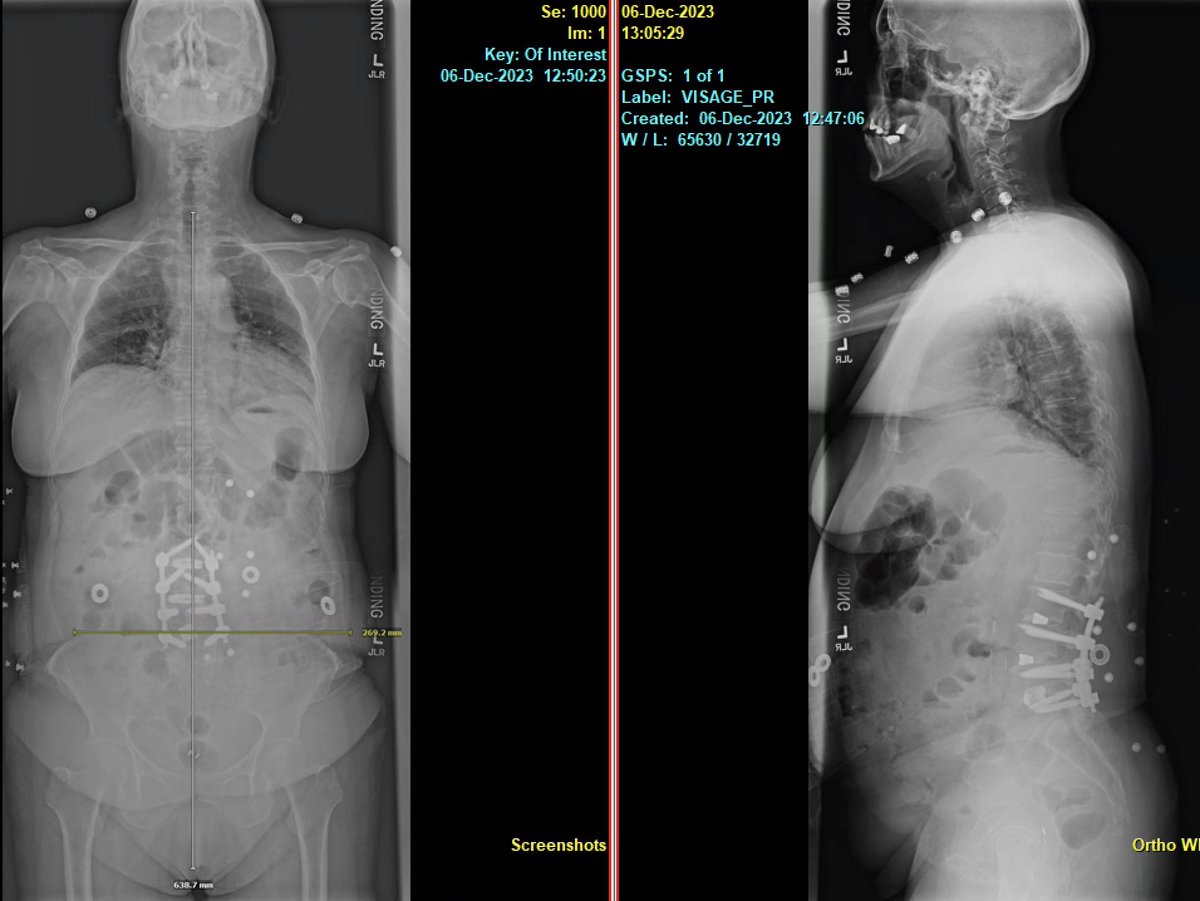

Awake MIS fusion to correct this patient scoliosis. @mayoclinic fellowship @RodNavarroM teaches endoscopic, lateral, MIS awake and deformity. Learn enabling technology & freehand. Accepting fellowship application for 2024-2025. @DoctorQMd @wchrisfox @oakinduroMD @StephenPirrisMD

Pre-and post-op awake MIS fusion to correct this patient scoliosis. @mayoclinic our associate surgeon @RodNavarroMD work hand in hand to learn the latest approach, enabling technology and freehand. Accepting applications for 2024-2025. @DoctorQMd @oakinduroMD @wchrisfox

Very satisfying case not only because of the deformity correction we achieved but more importantly because of the impact this surgery had on the patient’s life. @MayoClinicNeuro patient specific 3D printing for planning. https://t.co/Nz6Yehvu7Y! For new appointments #scoliosis